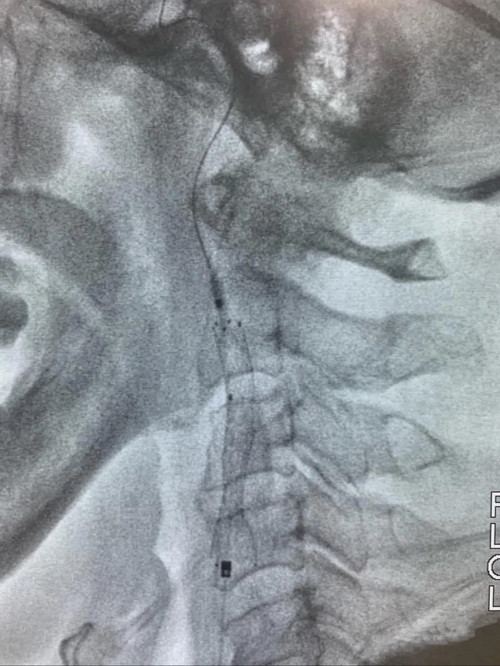

静脉溶栓治疗效果不明显,医生紧急启动介入治疗,为抢救患者生命争分夺秒。介入中心主任李光雷及副主任王振兴为患者急诊行血管造影检查,结果显示右颈内动脉起始段严重钙化斑块并闭塞。

右颈内动脉起始段严重钙化斑块并闭塞